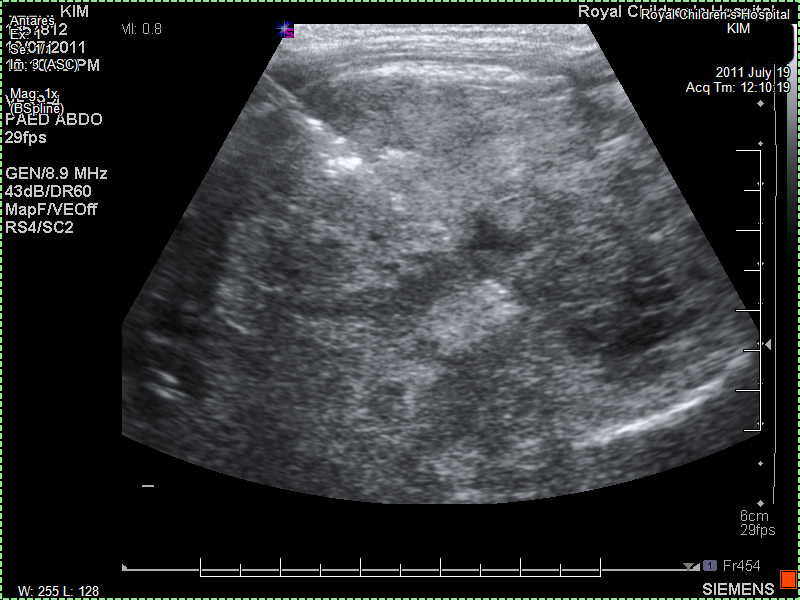

The paediatrician feels with her hands something in Kim's tummy. She gives us a gentle warning that there may be something there and refers us to a local imaging laboratory. She phones and makes sure we can be seen that same day. In the laboratory they ask us to wait. They tell us that there is an undefined mass near her left kidney. They don't want to say more. Ultrasounds are not that precise and we should go immediately back to the paediatrician. The paediatrician sees us almost immediately and tells us that it is not yet clear what Kim has but that it could be serious. At the same time she tries to comfort us with the knowledge that these days there are many new treatments. She doesn't want to use the word cancer but it is almost implied. She tells us she will refer us to the hospital to find out what it is exactly. The Monash is closer to us, but seen our previous experiences we ask to be referred to the Royal Children's Hospital. We insist that we have no trust in the Monash and will go to the Royal Children's. Which is traffic wise just a little further. The paediatrician mentions the close cooperation and that care should be the same. We are not convinced and the paediatrician is recognizes our resolve and understands why. She refers us to the Royal Children's Hospital emergency department with suspected cancer.

I have arranged an ultrasound scan of Kim's abdomen which shows a left sided mass, thought to be arising from her left kidney."